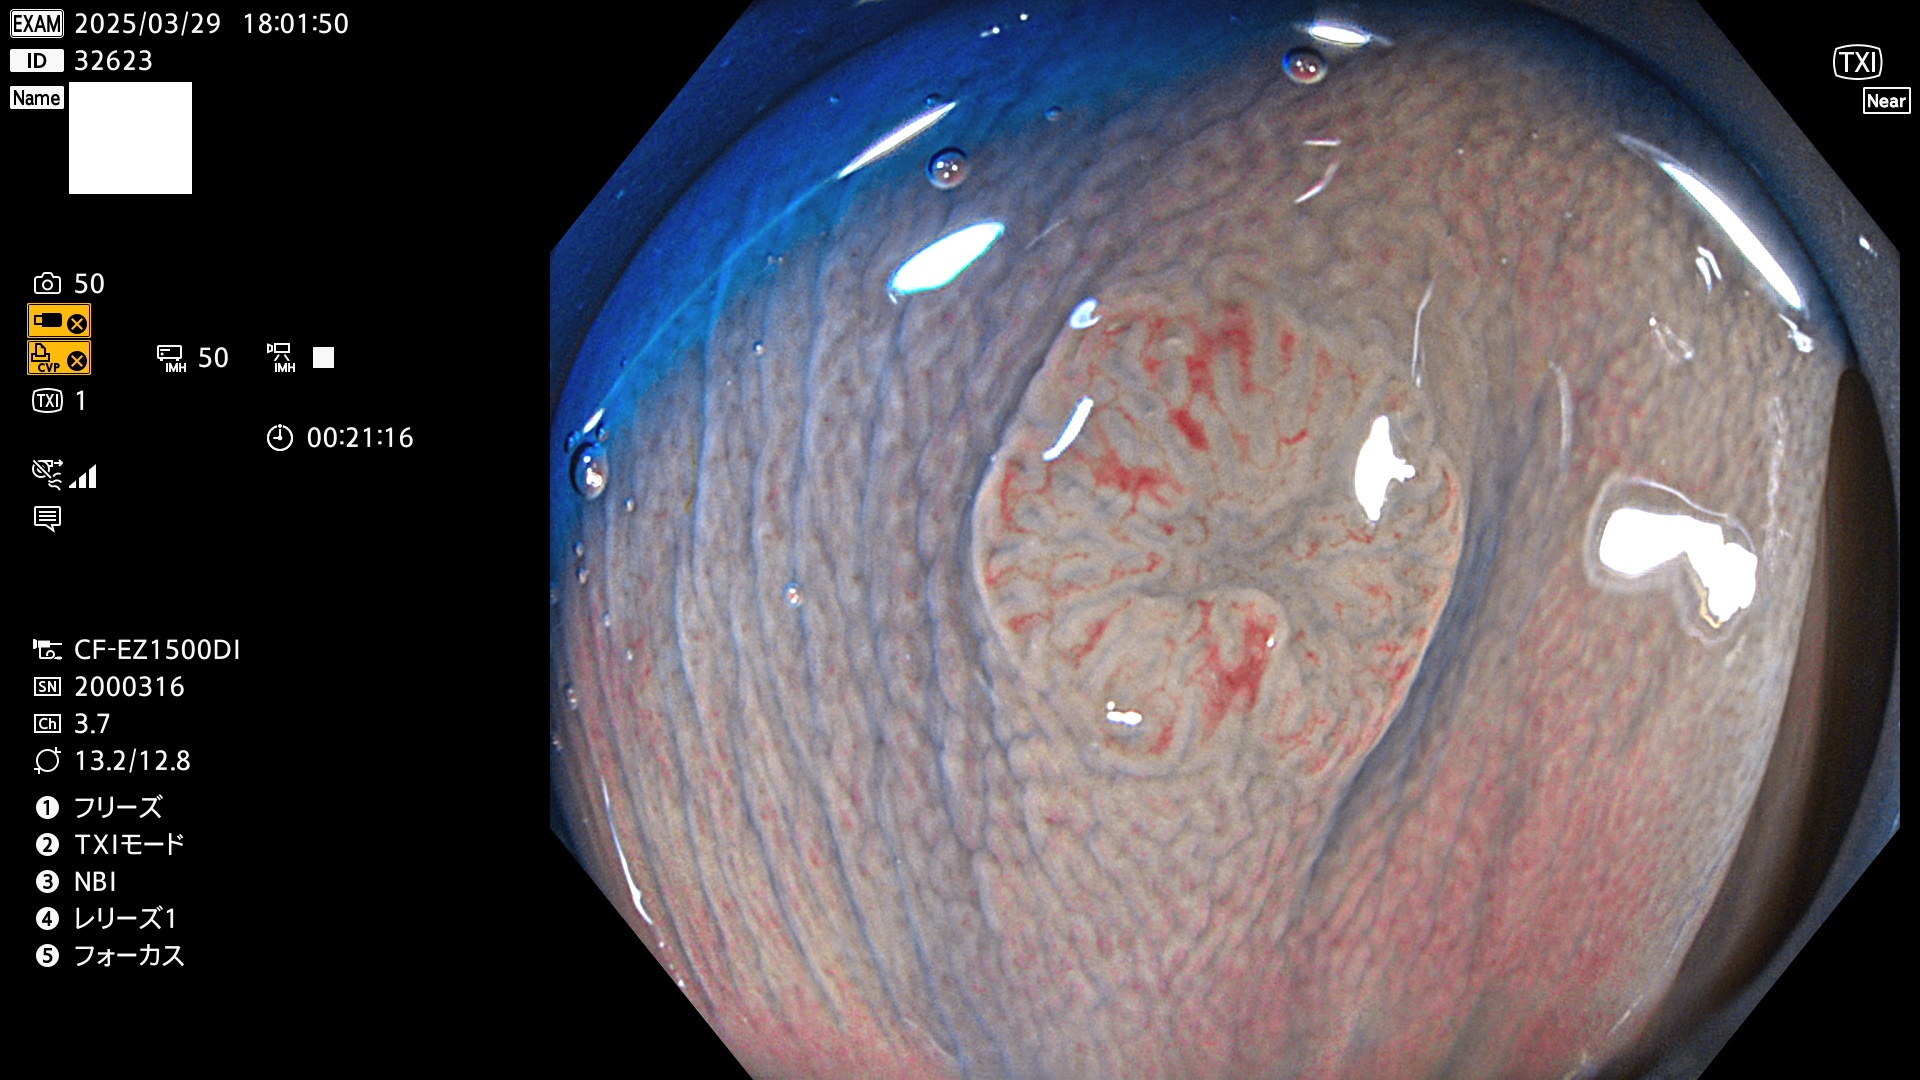

完全に平坦な物をUb、陥凹している物をUcと呼びます。Ubは認識が困難で、Ucはびらん(炎症)と紛らわしいために見落とされやすく、「内視鏡後・大腸癌」の原因になります。

抽出の対象期間 2025年3月27日〜3月30日の4日間(48件の検査)8個 (8/48=16%)